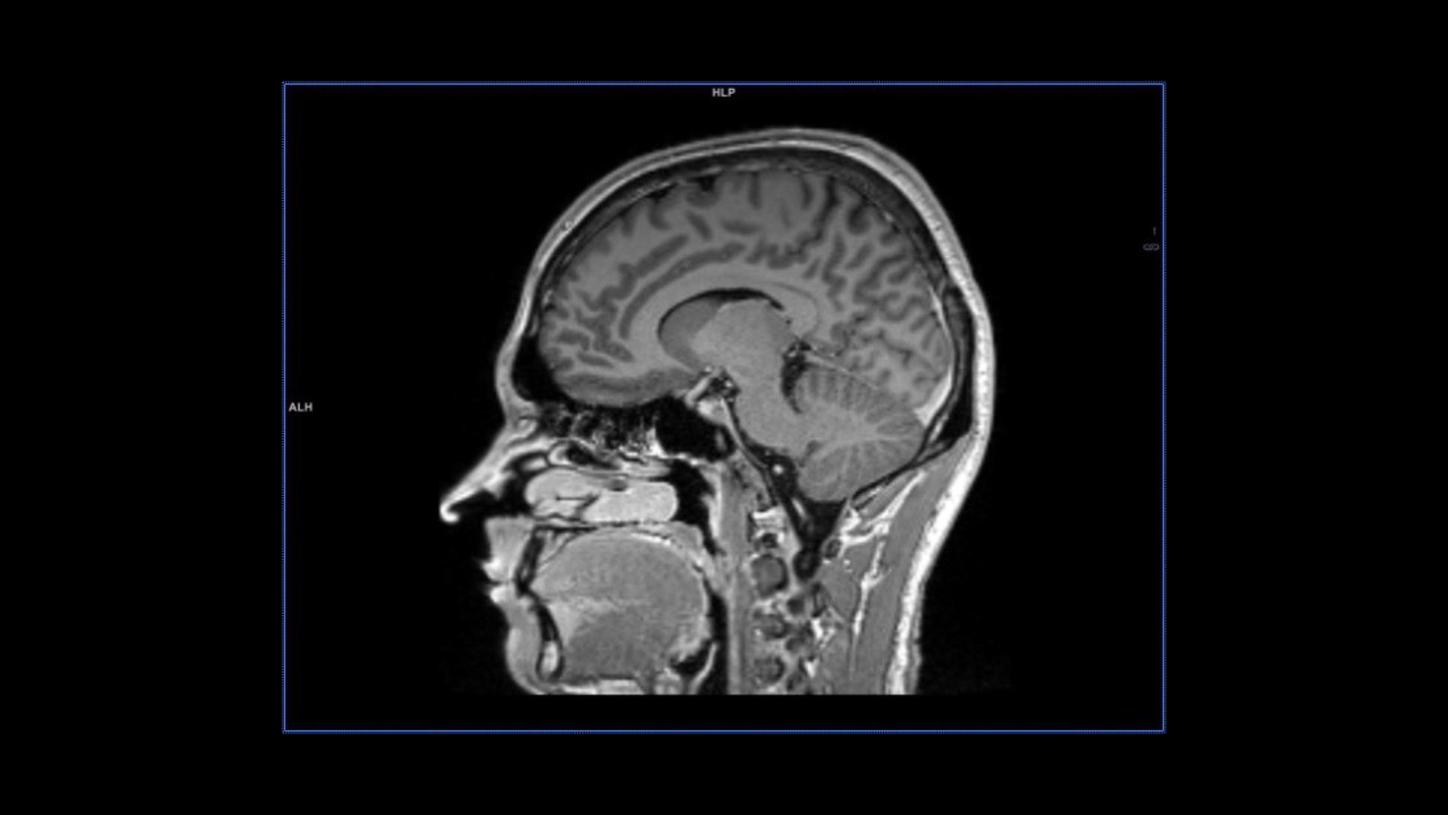

MAGNETOM Sola: T1 contrast sagittal MPRAGE

MAGNETOM Sola: T1 contrast sagittal MPRAGE